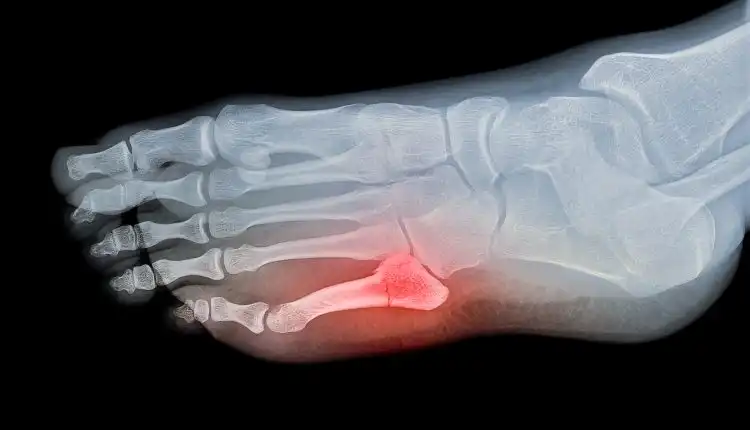

Ketika tulang mendapatkan tekanan luar yang diberikan padanya, seperti pukulan atau terjatuh, ada potensi bahwa tulang tidak dapat menahan jumlah tekanan dan akhirnya retak. Hilangnya integritas itu mengakibatkan tulang retak. Penting untuk diingat bahwa tulang retak atau patah semuanya menggambarkan situasi yang sama, cedera pada tulang yang telah rusak. Patah ataupun retak pada tulang, semuanya memiliki arti yang sama.

Jenis Tulang Retak Apa yang Paling Umum?

Fraktur biasanya digambarkan berdasarkan lokasinya, bagaimana tulang disejajarkan, apakah ada komplikasi terkait dengan fungsi darah dan saraf, dan apakah kulit utuh di lokasi cedera. Istilah dan definisi yang digunakan dalam pengobatan untuk menggambarkan tulang retak memungkinkan para profesional perawatan kesehatan untuk menjelaskan secara tepat di mana letak tulang retak tersebut.